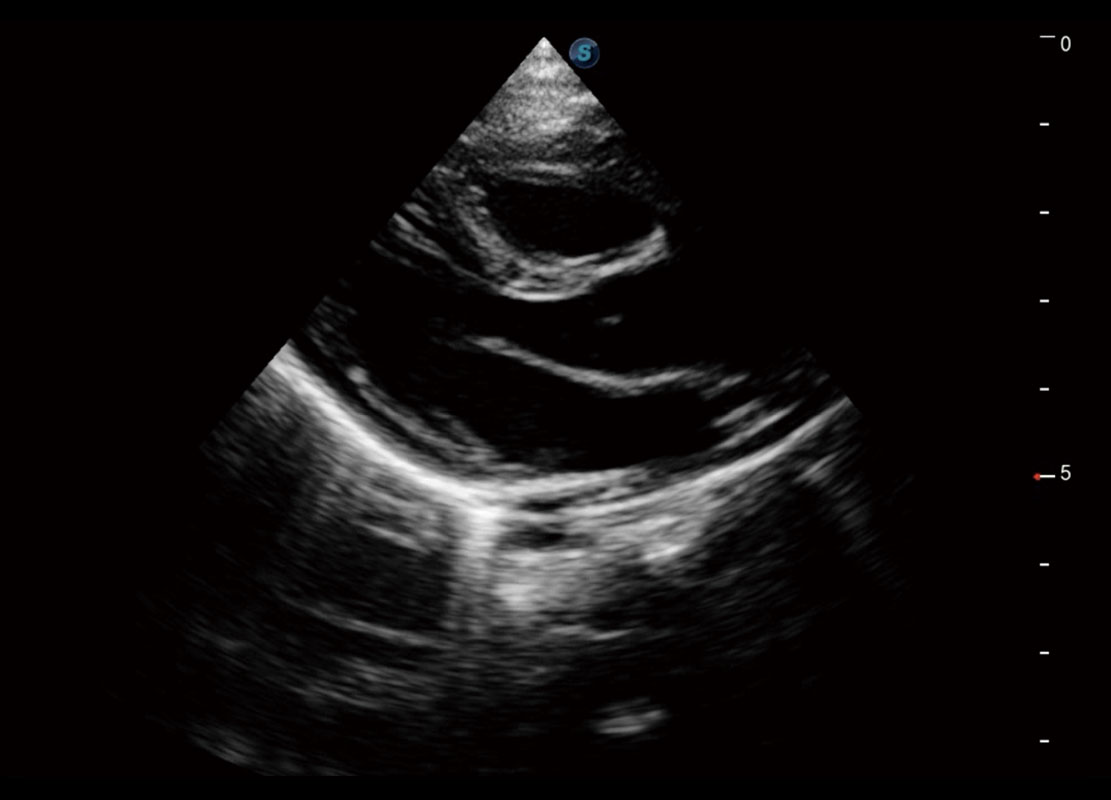

P60搭载一系列胎儿心脏成像技术,实现精细的胎儿心脏评估。

• 四腔切面

• 四腔心血流

中晚孕筛查

P60提供简单易学易用的高端诊断工具,为您中晚孕筛查提供快速清晰的解剖信息。